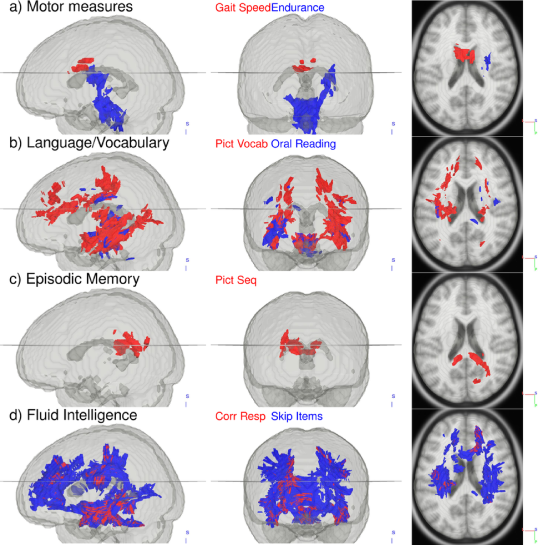

The HCP ODFs also correlate with neurocognitive measures (Fig. 10 and 11). Walking endurance (Fig. 10a and 11a) predictably relates to the corticospinal tract, while the frontal part of the corpus callosum indicated in gait speed has been identified before when comparing endurance athletes with non-athletes (Raichlen et al., 2016) and when studying the effect of treadmill training after stroke (Enzinger et al., 2009). Language recognition and comprehension tasks (Fig. 10b and 11b), as measured by the Oral Reading and Picture Vocabulary test, correlate with ODFs in areas identified by fMRI work (Berl et al., 2010): posterior superior temporal gyrus and inferior frontal gyrus connected by stretches of the arcuate fasciculus pathway/superior longitudinal fasciculus III. Besides these areas, language comprehension also relates with ODFs in the medial frontal gyri and the left precuneus (Schmithorst et al., 2007). Our analysis further connects the Episodic Memory measure with the posterior cingulate and precuneus, though not with the medial temporal cortex (Fig. 10c and 11c). These areas have been shown to deactivate in episodic memory tasks (Dickerson and Eichenbaum, 2010). Lastly, Fluid Intelligence correlates widely with ODFs in the prefrontal, parietal and temporal cortex as indicated before (Gray et al., 2003) as well as with ODFs along tracts connecting these regions (Fig. 10d and 11d).